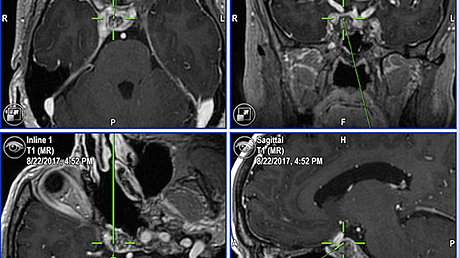

Initial MR images of the brain showed no remarkable changes (Figure 1A). Electroencephalogram revealed triphasic waves.

She developed status epilepticus and was intubated on the third hospital day. MR images on day 11 showed symmetric abnormal signal intensity in the insular and cingulate cortices bilaterally, which suggested the toxic effect of accumulated ammonia (Figure 1B).

Her consciousness improved slightly after extubation on day 13, when the plasma ammonia level was 32 μg/dL. The abnormal signal intensity on the brain MR images partially improved on day 24, but her disorientation remained (Figure 1C). She was transferred to a long-stay hospital to continue rehabilitation on day 52.